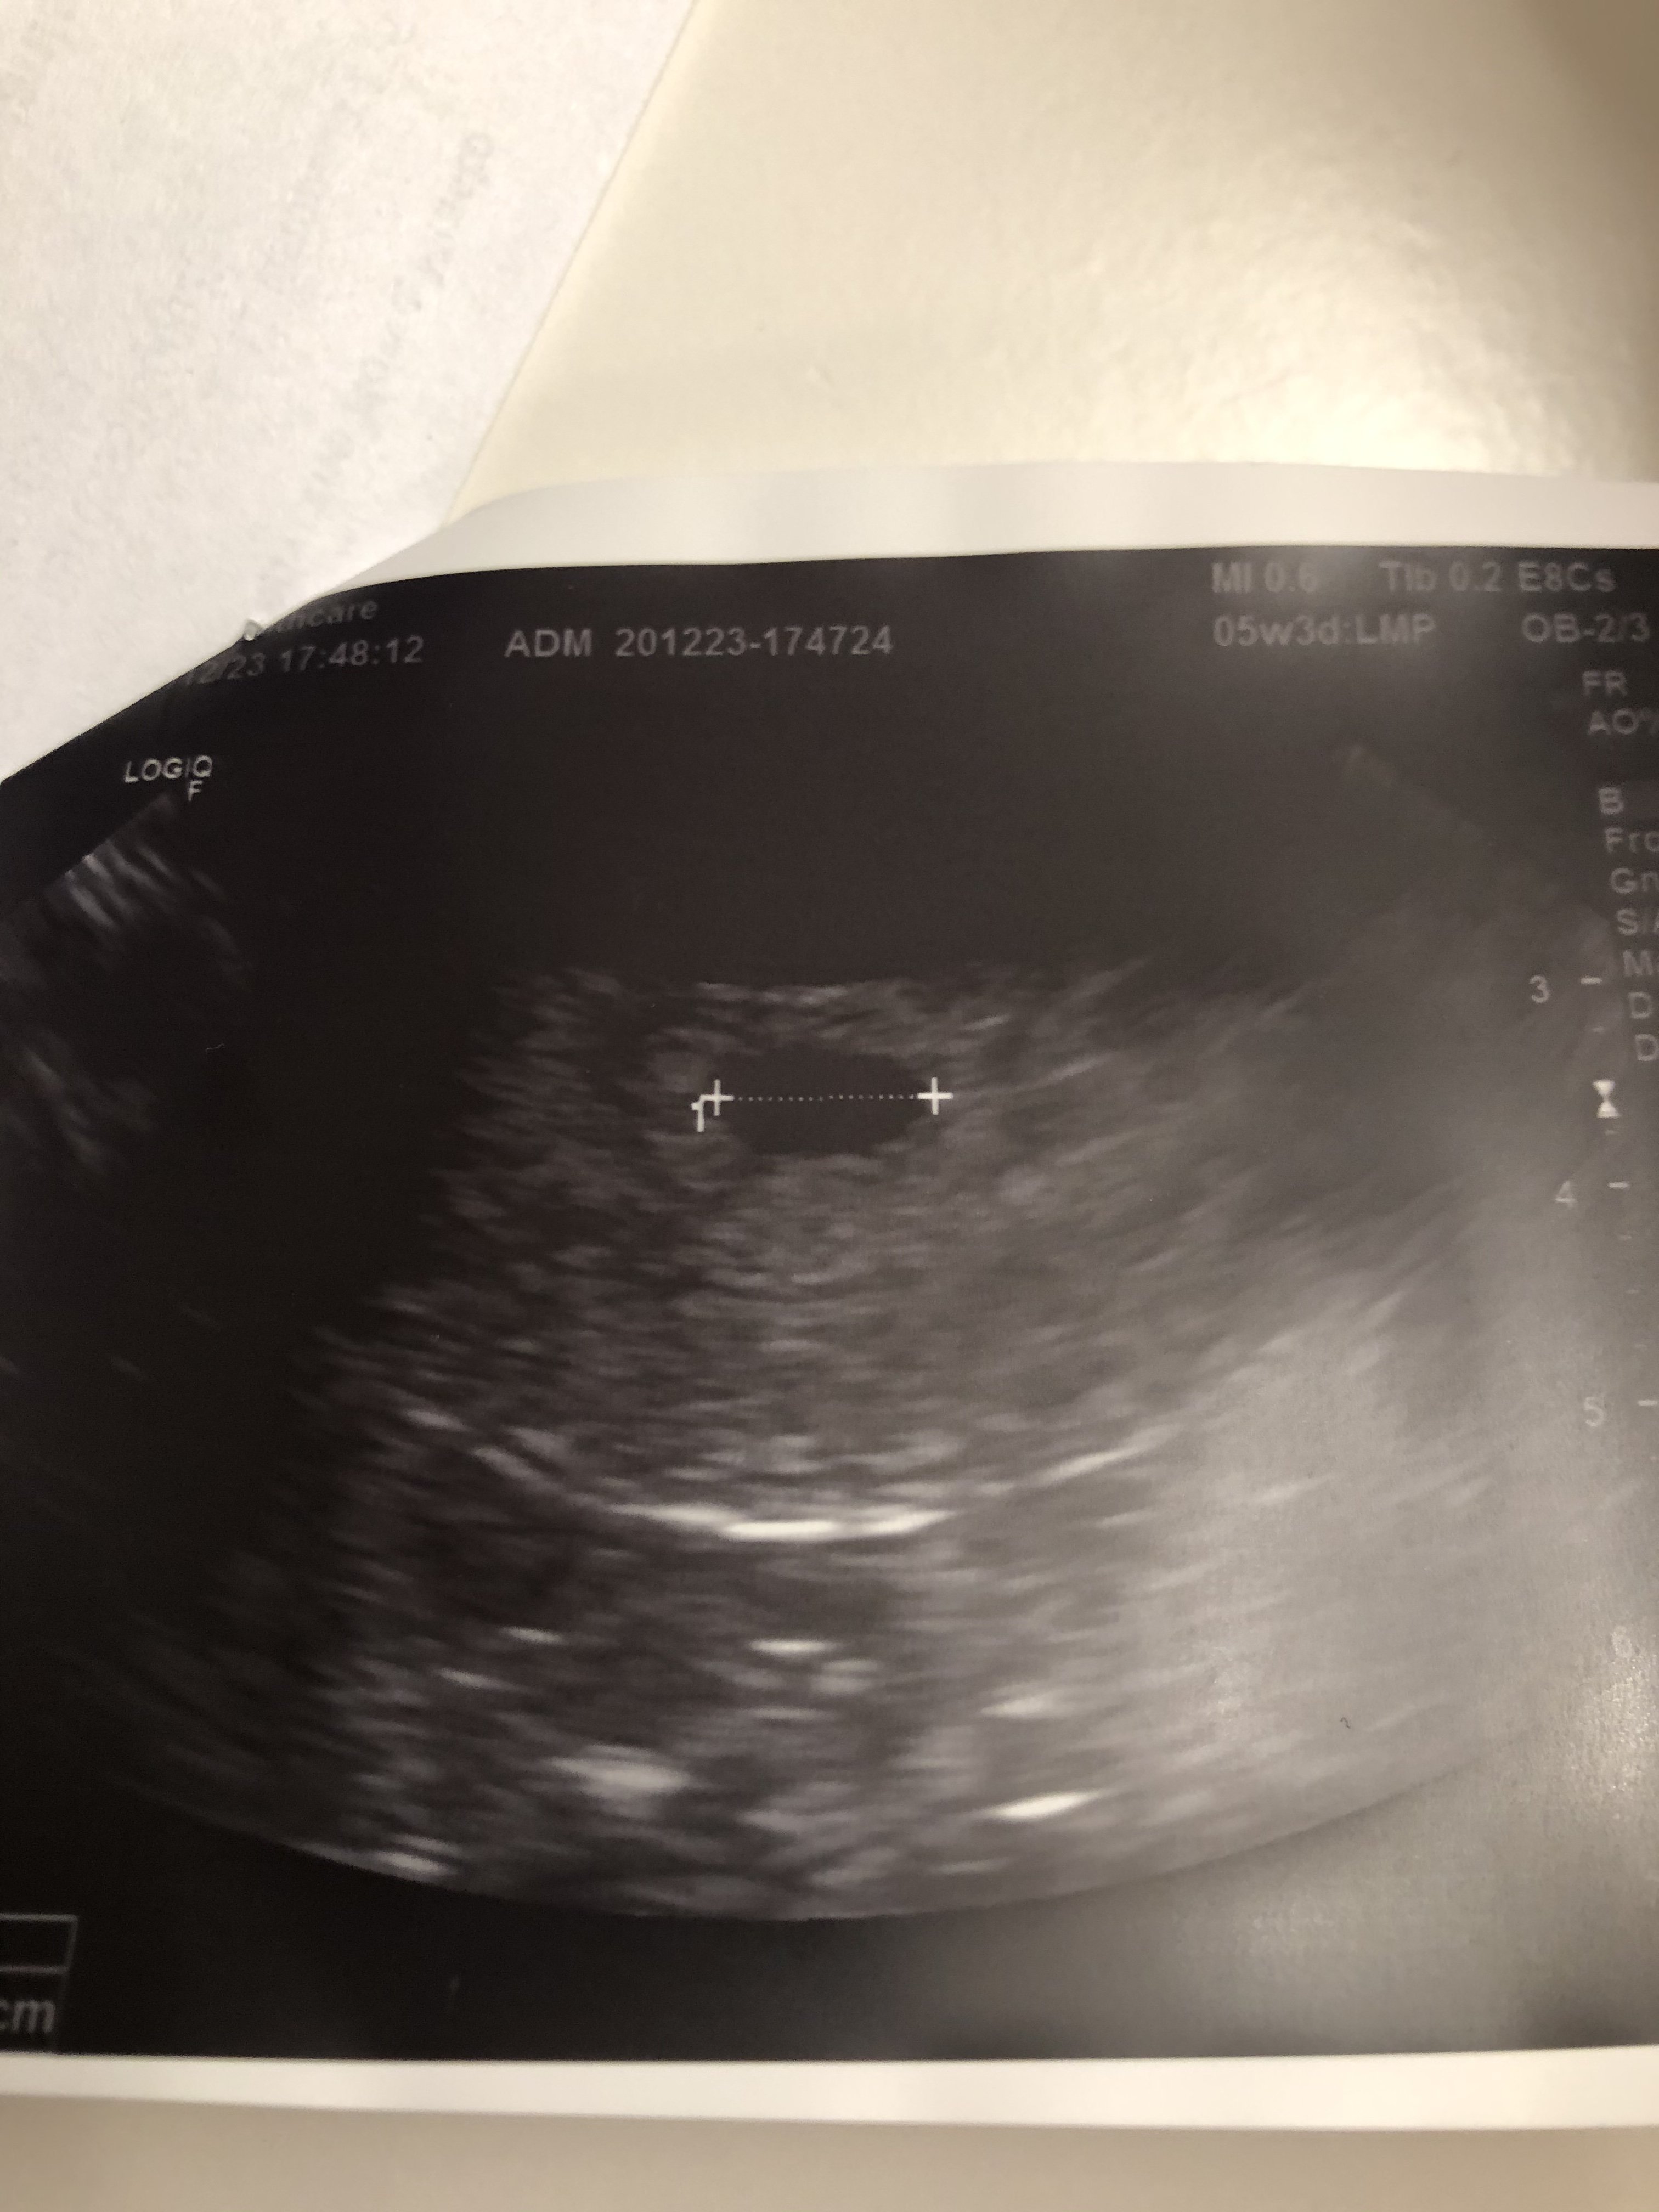

Podobno na usg widać coś od bety 1000@kruszynka22 a jaki poziom bety?

Dziewczyny mam wyniki, w piątek było 11 dni po i 47, dzisiaj 502. Mam dzisiaj tą wizytę u lekarza, ale chyba nie będzie nic widać i chyba odwołam tą wizytę, chociaż 2 godziny zostało [emoji26]Zobacz załącznik 1218379